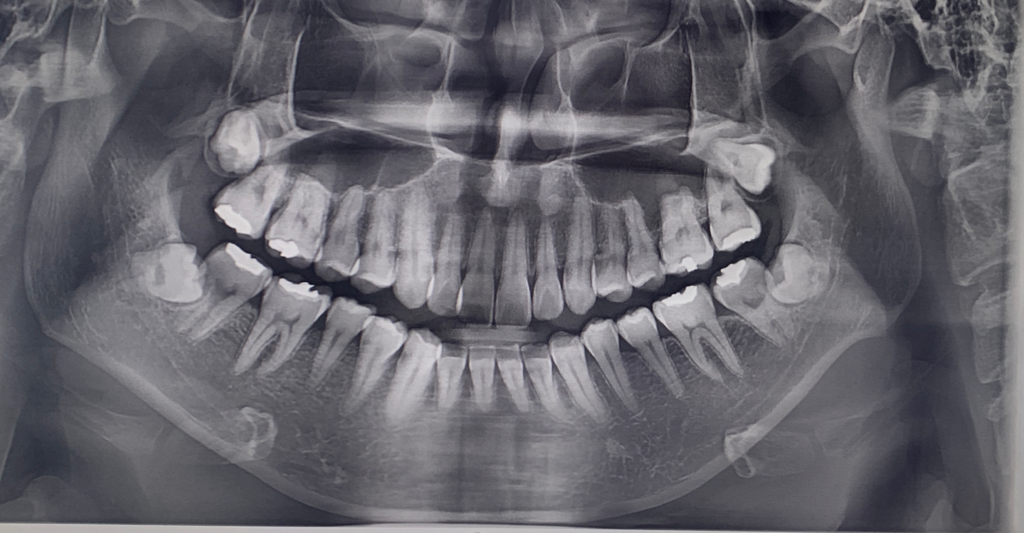

교정치료 후 치근흡수 문의드립니다

1. 현재 제 치아의 뿌리 상태가

어떠한지 궁금합니다.

현재 교정중에 있는데요. 교정을 하게되면 치근이 흡수되어 짧아지는 현상이 필연적이라고 하여

궁금합니다.

치근흡수되어 짧아지면 많이 흔들릴 정도의 뿌리인가요?